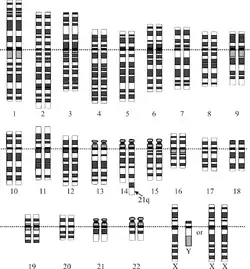

La trisomie 21 est une anomalie chromosomique définie par la présence d'un 3e exemplaire plus ou moins complet du chromosome 21, le plus petit des chromosomes. Dans 95 % des cas, il s'agit d'une trisomie 21 dite « libre » (par non-disjonction méiotique) et homogène. Dans 2 à 3 % des cas restants, il s'agit d'une mosaïque, et dans 2 à 3 % des cas restants également, il s'agit d'une trisomie dite « non libre », c'est-à-dire que la partie surnuméraire du chromosome 21 est fusionnée avec un autre chromosome[13].

Le diagnostic ne peut se faire que par la mise en évidence du chromosome 21 supplémentaire lors d'un examen génétique, généralement par analyse du caryotype ou par hybridation in situ en fluorescence.

La présence d'un troisième chromosome 21 est la cause de la pathologie. Le mécanisme de la présence du chromosome supplémentaire est important à connaître pour le conseil génétique. La réalisation du caryotype permet de connaître le mécanisme.

La formule chromosomique de la personne atteinte de trisomie 21 est donc : « 47, 21+ ».

Durant l'année 1959, la trisomie mongolienne est confirmée par des chercheurs anglais, américains et suédois. En avril 1960, une commission internationale, dite de Denver, propose de classer les chromosomes humains en numéros selon leur taille et leur aspect, c'est ainsi que le numéro 21 a été attribué aux chromosomes de la trisomie mongolienne[72].

En 1993, une étude suggère que les gènes liés aux caractéristiques importantes du syndrome de Down se trouvent dans une région critique du bras long du chromosome 21, définie en 1997 comme DCR-1 (Down Critical Region-1) bientôt subdivisée en sous-régions. Dans le cadre du Projet Génome Humain, le séquençage du chromosome 21 est publié en 2 000, c'est le second chromosome humain décodé après le chromosome 22[17].

La trisomie 21 se définit alors comme surexpression de certains gènes, situés sur une région (21q21 à 21q22.3) du bras long du chromosome 21, dont les plus importants contrôlent le développement des structures cérébrales et cardiaques. Ce qui ouvre des perspectives thérapeutiques par recours à des inhibiteurs de la surexpression des gènes en cause[27],[17].